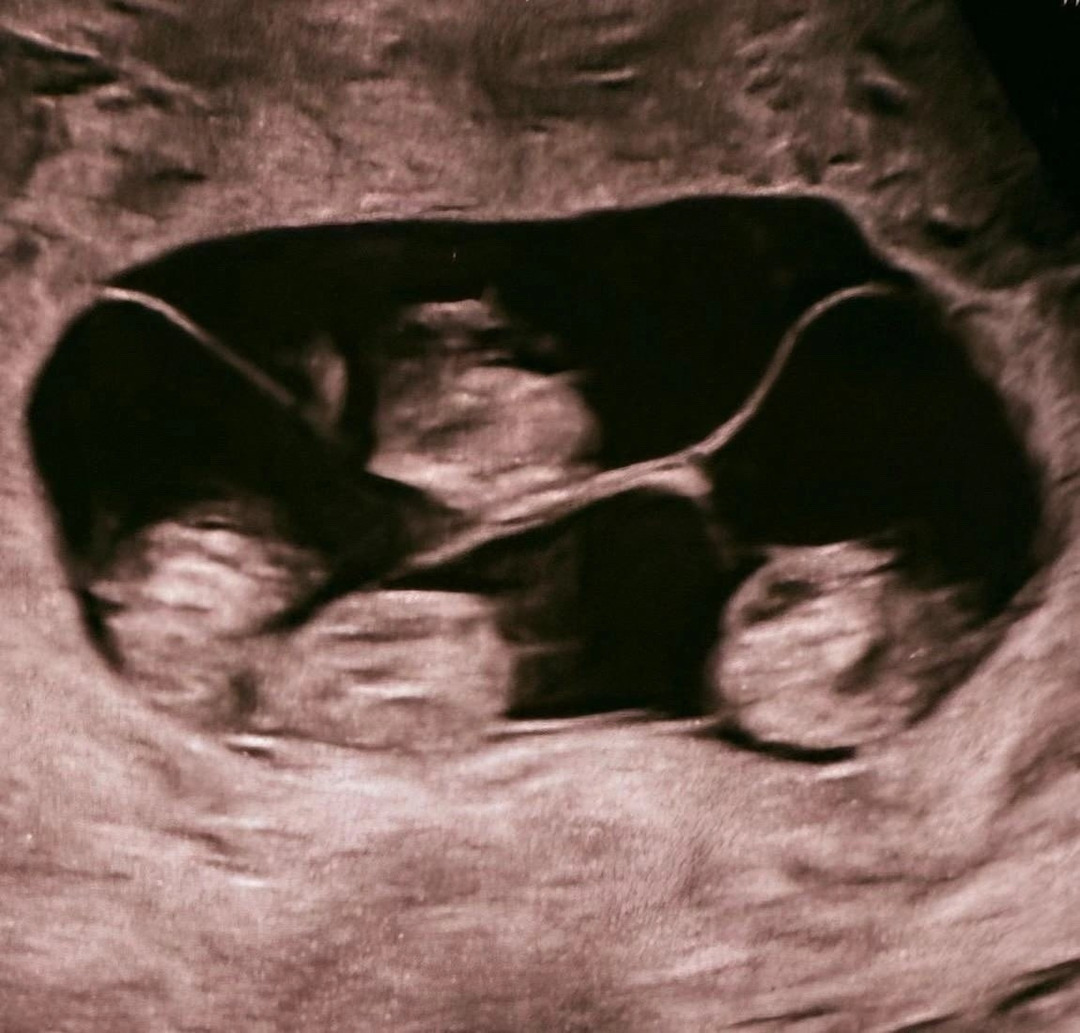

В России впервые женщина из Петербурга родила четверых девочек-близняшек. Это событие имеет вероятность 1 на 15,5 млн родов.

Малышки идентичны и находятся под наблюдением врачей. В мире известно около 15 идентичных случаев рождения четверняшек, из которых 10 — девочки.